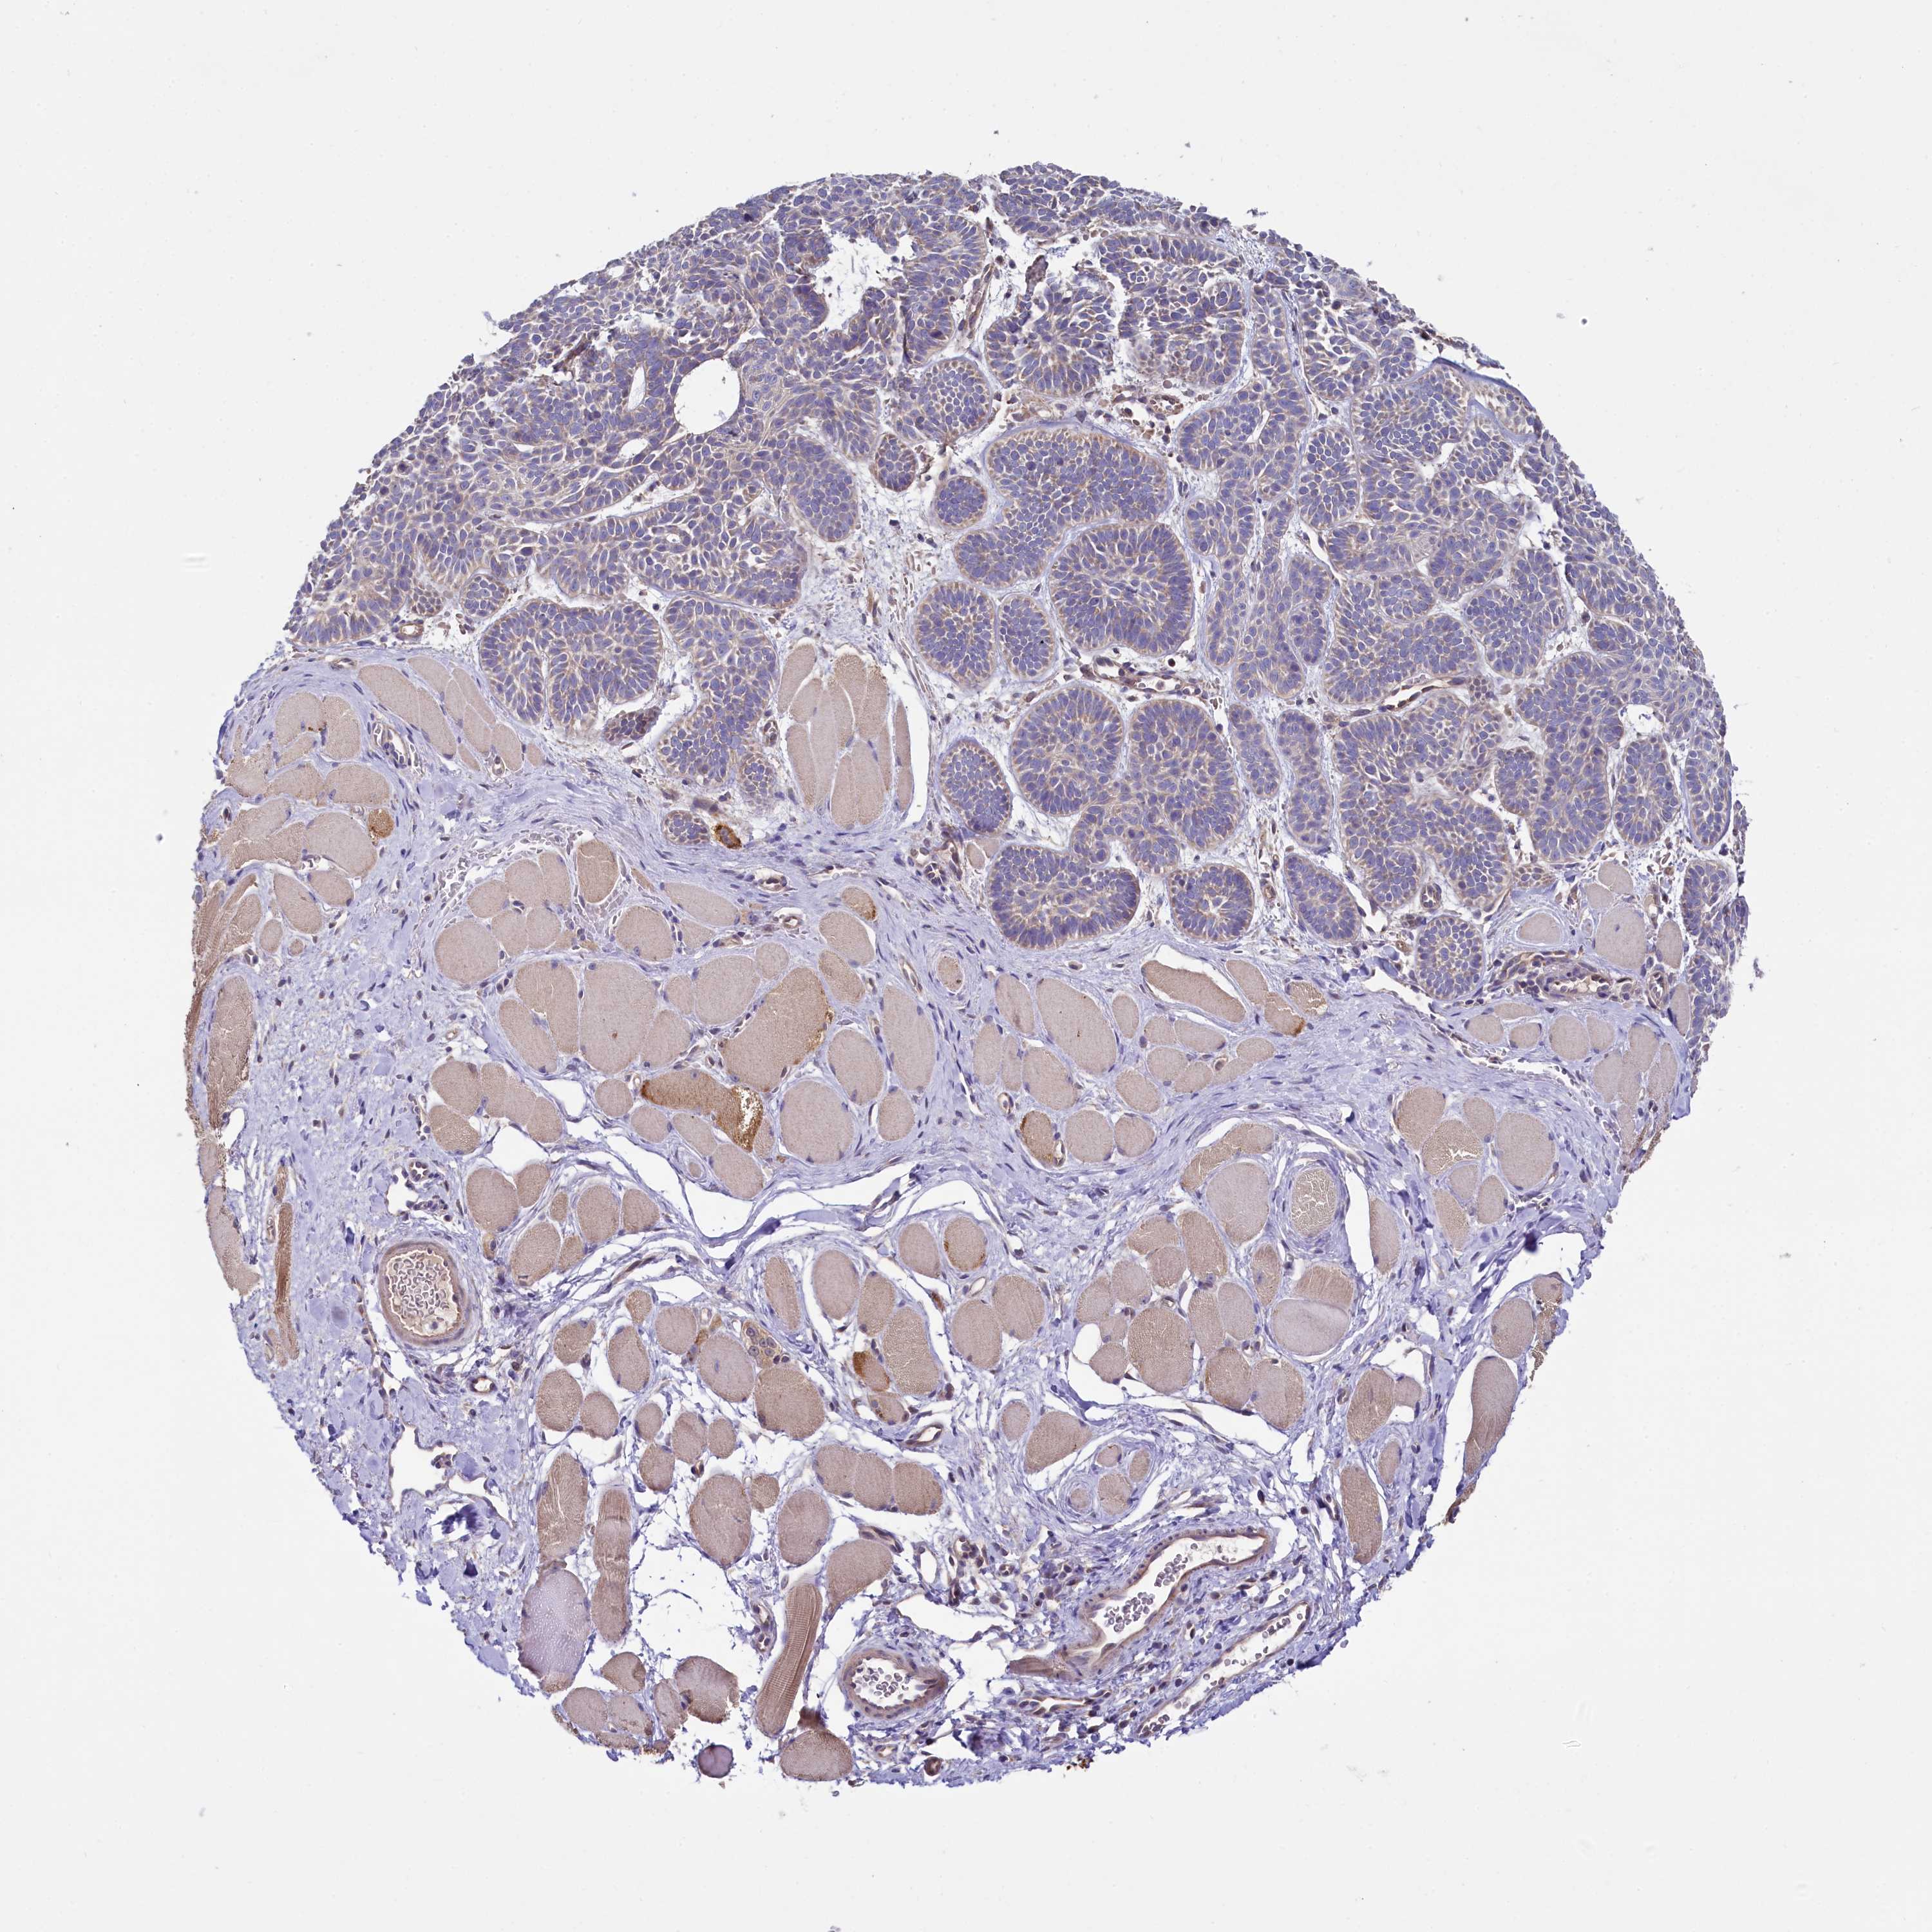

SKIN CANCER - Protein expressioni

A mouse-over function shows sample information and annotation data. Click on an image to view it in a full screen mode. Samples can be filtered based on level of antibody staining by selecting one or several of the following categories: high, medium, low and not detected. The assay and annotation is described here.

Each image is clickable and will lead to virtual microscopy that enables deeper exploration of all samples and also displays staining intensity scores, fraction scores and subcellular localization as well as patient and tissue information for each sample.

Antibody HPA039779

Basal cell carcinoma